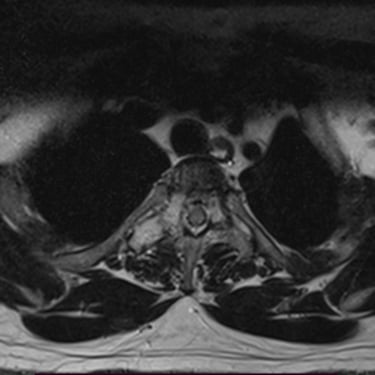

Tumor vertebral dorsal hemorrágico: descompresión medular, biopsia y artrodesis dorsal

El tumor vertebral dorsal puede ocasionar compresión de la médula espinal, dolor intenso y alteraciones neurológicas progresivas. En algunos casos, estos tumores presentan componente hemorrágico que incrementa la presión sobre las estructuras nerviosas. El tratamiento quirúrgico puede incluir descompresión medular para liberar la médula espinal, toma de biopsia para establecer el diagnóstico histopatológico y artrodesis dorsal con instrumentación para estabilizar la columna vertebral. Este abordaje permite reducir el riesgo de daño neurológico, aliviar los síntomas y mantener la estabilidad vertebral. La cirugía se realiza con técnicas especializadas que buscan preservar la función neurológica y mejorar la calidad de vida del paciente.